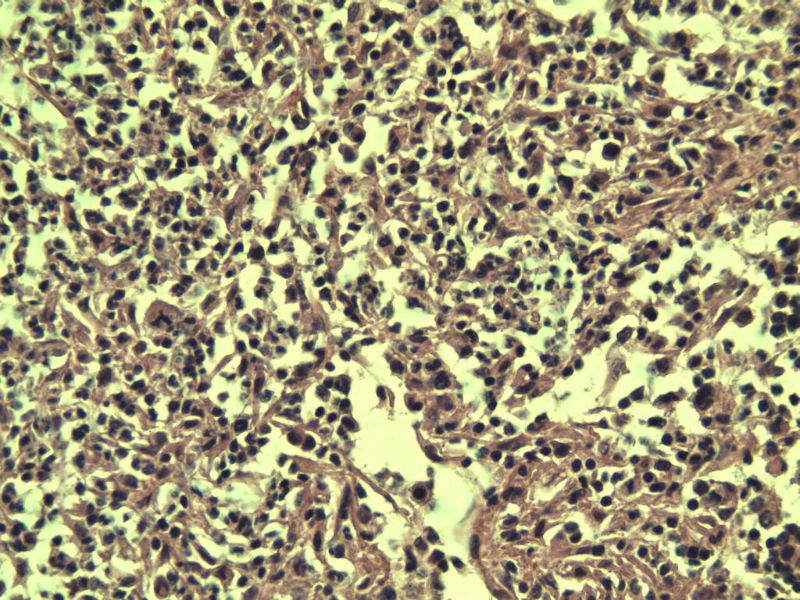

男,38岁,腹股沟 多枚淋巴结活检  直径 0.2-0.5 请各位老师看看 是什么 谢谢了!

"畏寒,发热咳嗽1年,加重伴腹部疼痛2月" 2月前患者感腹部疼痛不适伴大便呈稀大便,量不详,伴腰骶部疼痛,胸片:纵膈及右肺门多发性淋巴结肿大,进一步完善胸部CT:右肺及中叶病变,纵膈及肺门多发淋巴结肿大,结核性可能,脾脏增大,PPD(-),1个月来患者出现中上腹食欲不振,体重进行性消瘦,全身疲乏无力,3天前到医学院就诊,腹部B超:右肝囊肿,胆囊壁毛糙,脾大,胰周多个减弱回声,淋巴结不能除外,腹水,血常规示:WBC16.36x109 /L,N%14.25%,RBC2.63x1012/L ,HGB 66g/L 。右侧腋窝及腹股沟可扪及多枚淋巴结,压痛,无明显粘连。

腹股沟 多枚淋巴结活检图3

副皮质区增生,纤维化显著,细胞呈多形性,有一些多核巨细胞及一些异型细胞,病理性核分裂易见,胞浆红染,散在的小淋巴细胞,T细胞淋巴瘤不能除外,树突细胞肉瘤等鉴别。免疫标记。CD21、CD3、CD5、CD10、CD20、CD79a、PD1、CD68、CXCL13、KI-67、CD68、CD163等,据切片选择。不知对否。

淋巴结正常结构破坏,可见大的异型细胞,上皮样或梭形,恶性肿瘤,依据病史,首先考虑淋巴造血系统疾病,大中小细胞混杂,大细胞多,形态多样,可见多核瘤细胞,除以上考虑外需鉴别间变大、组织细胞肉瘤、指状突/树突细胞肿瘤、HL等,还需排除肉瘤或癌转移,尽管病人年轻,加上ALK、CK、S-100、CD1a。